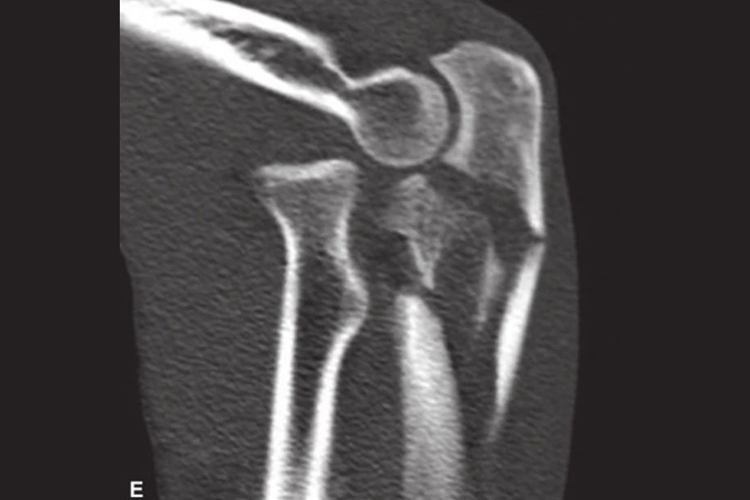

CT照片

胳膊骨折CT照片可显示胳膊骨折部位、骨块大小及移位情况,有时还会出现断端错位,肱桡关节脱位。胳膊包含肱骨、尺骨、桡骨三部分,桡骨和尺骨是紧靠在一起的顶端相反的两个锥形体,相互平行,被近端丰富的肌肉组织紧裹在一起。由于桡骨和尺骨接触紧密,所以在遭受外伤时,容易骨折。